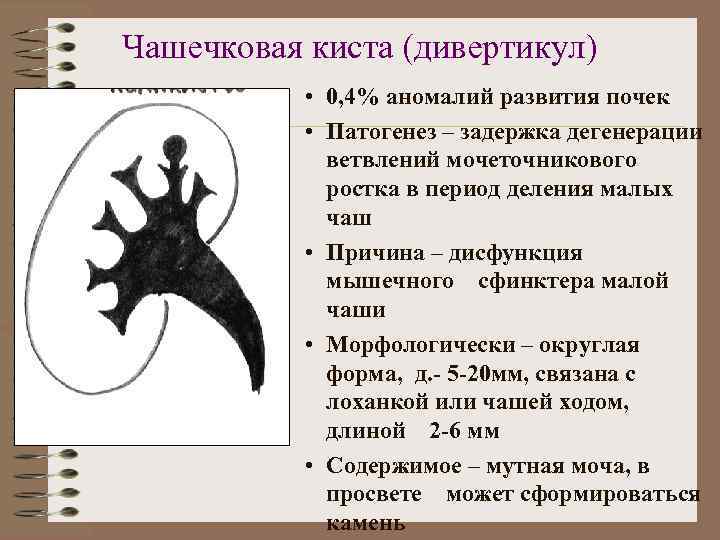

Чашечковая киста (дивертикул) • 0, 4% аномалий развития почек • Патогенез – задержка дегенерации ветвлений мочеточникового ростка в период деления малых чаш • Причина – дисфункция мышечного сфинктера малой чаши • Морфологически – округлая форма, д. - 5 -20 мм, связана с лоханкой или чашей ходом, длиной 2 -6 мм • Содержимое – мутная моча, в просвете может сформироваться камень